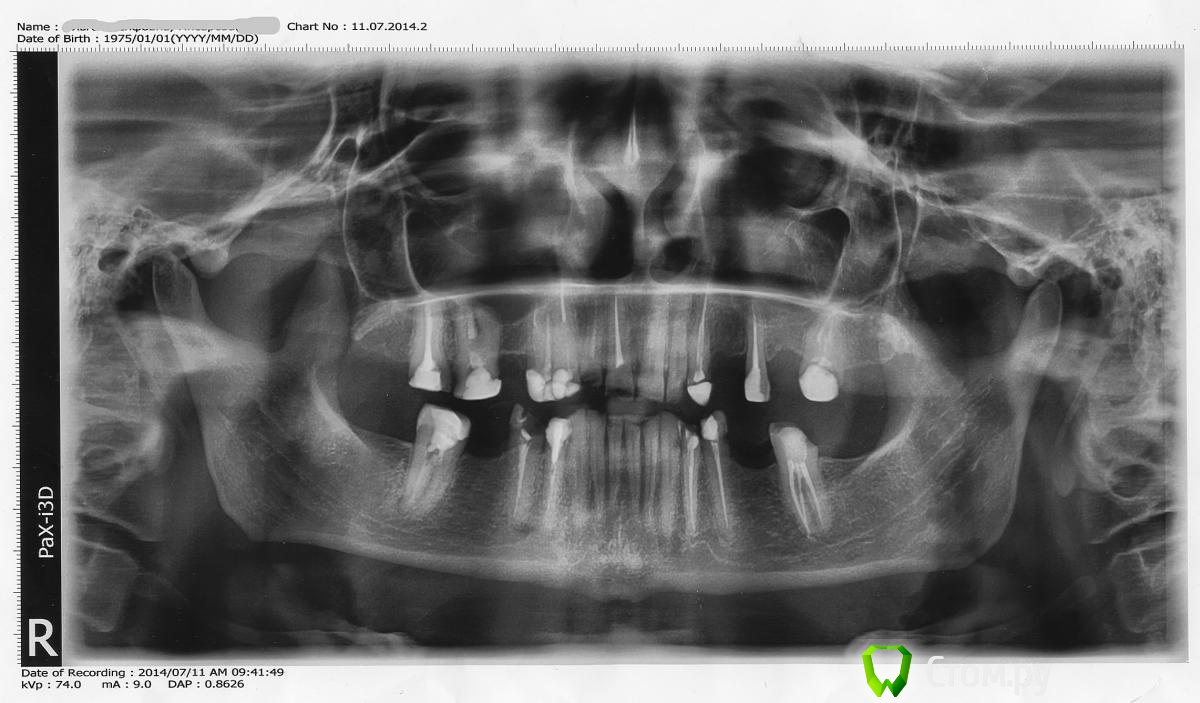

Vitremer Опубликовано 18 июля, 2014 Автор Поделиться Опубликовано 18 июля, 2014 Снимок Ссылка на комментарий

Евгений Ходыкин Опубликовано 13 июля, 2014 Поделиться Опубликовано 13 июля, 2014 Имхо 1.7, 1.6, 1.2 аут, судьба остальных после рентгена... Ссылка на комментарий

Евгений Ходыкин Опубликовано 13 июля, 2014 Поделиться Опубликовано 13 июля, 2014 2.7 туда же Ссылка на комментарий

M@estro Опубликовано 13 июля, 2014 Поделиться Опубликовано 13 июля, 2014 Заново чем?- вкв , анкера, билд-апы по Бабурову? (я так вижу кругового феррула нет) Анкера в топку,остальное- оценил бы ,что там от зубов осталось после того,как убрал. Сложно судить,но что -то мне подсказывает,что покрывать всё это в нынешнем состоянии - это не совсем правильно и не совсем надолго Ссылка на комментарий